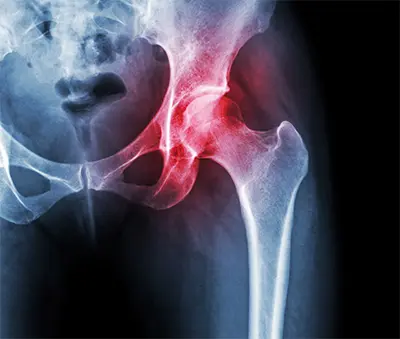

Avascular necrosis (AVN), also called osteonecrosis, is a condition where bone tissue dies because it does not receive enough blood flow. This can happen when a bone fracture or joint dislocation damages nearby blood vessels. The hip joint is most commonly affected, particularly the head of the femur (thighbone), though the knee and shoulder can also be involved.

The most common risk factors for AVN include chronic use of high-dose steroid medications and heavy alcohol use. In some cases, the condition develops after an injury. Early in AVN, small breaks may appear in the bone, and over time the bone can collapse, causing significant pain.

Dr. Benjamin Domb and his team diagnose AVN using imaging techniques such as X-rays, MRI scans, and bone scans to confirm the condition and rule out other causes of joint pain.